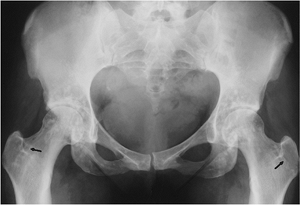

![]() |

FIGURE 15-2

Osteopoikilosis. AP radiograph of the pelvis and hips showing multiple small sclerotic foci in the proximal femora, ischia, and acetabuli. Note the femoral striations (arrows) (osteopathia striata is related to osteopoikilosis). |